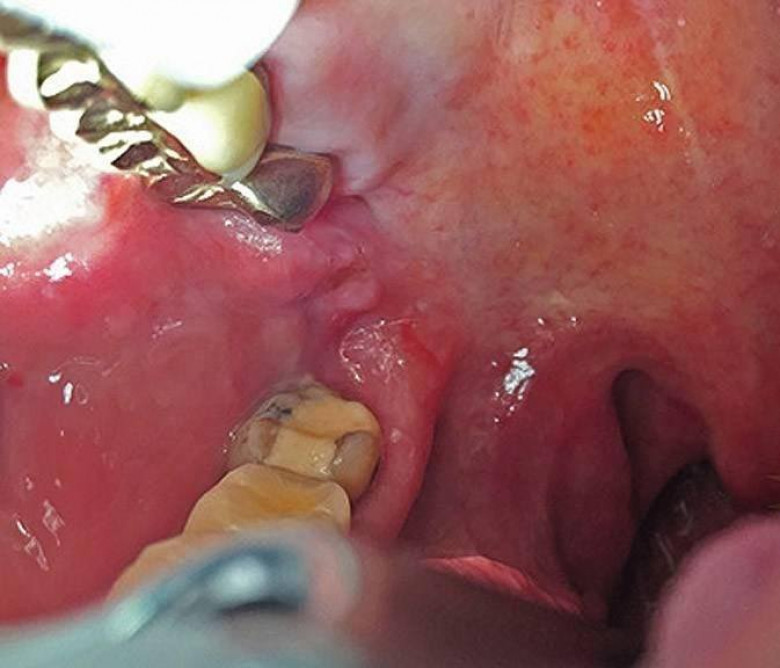

LifestyleՀամբուրգի 65-ամյա բնակչուհին դիմեց բժիշկներին՝ ասելով, որ չի կարողանում գտնել ատամները լվանալու ժամանակ կորցրած էլեկտրական խոզանակի կտորը: Բժիշկները նախ հետազոտեցին կնոջ ստամոքսն ու աղիները, բայց ոչինչ չհայտնաբերեցին և նրան ուղարկեցին տուն: Բայց մի քանի օր անց կինը կրկին դիմեց հիվանդանոց՝ գանգատվելով, որ ոչինչ չի կարողանում ուտել: Դիմածնոտային վիրաբույժը կնոջ բերանի խոռոչի փափուկ հյուսվածքներում 6 սմ երկարությամբ օտար առարկա նկատեց: Պարզվեց, որ դա հենց ատամի խոզանակի ջարդված կտորն էր: Վիրահատությունից հետո մի քանի օր անց կինը դուրս գրվեց: